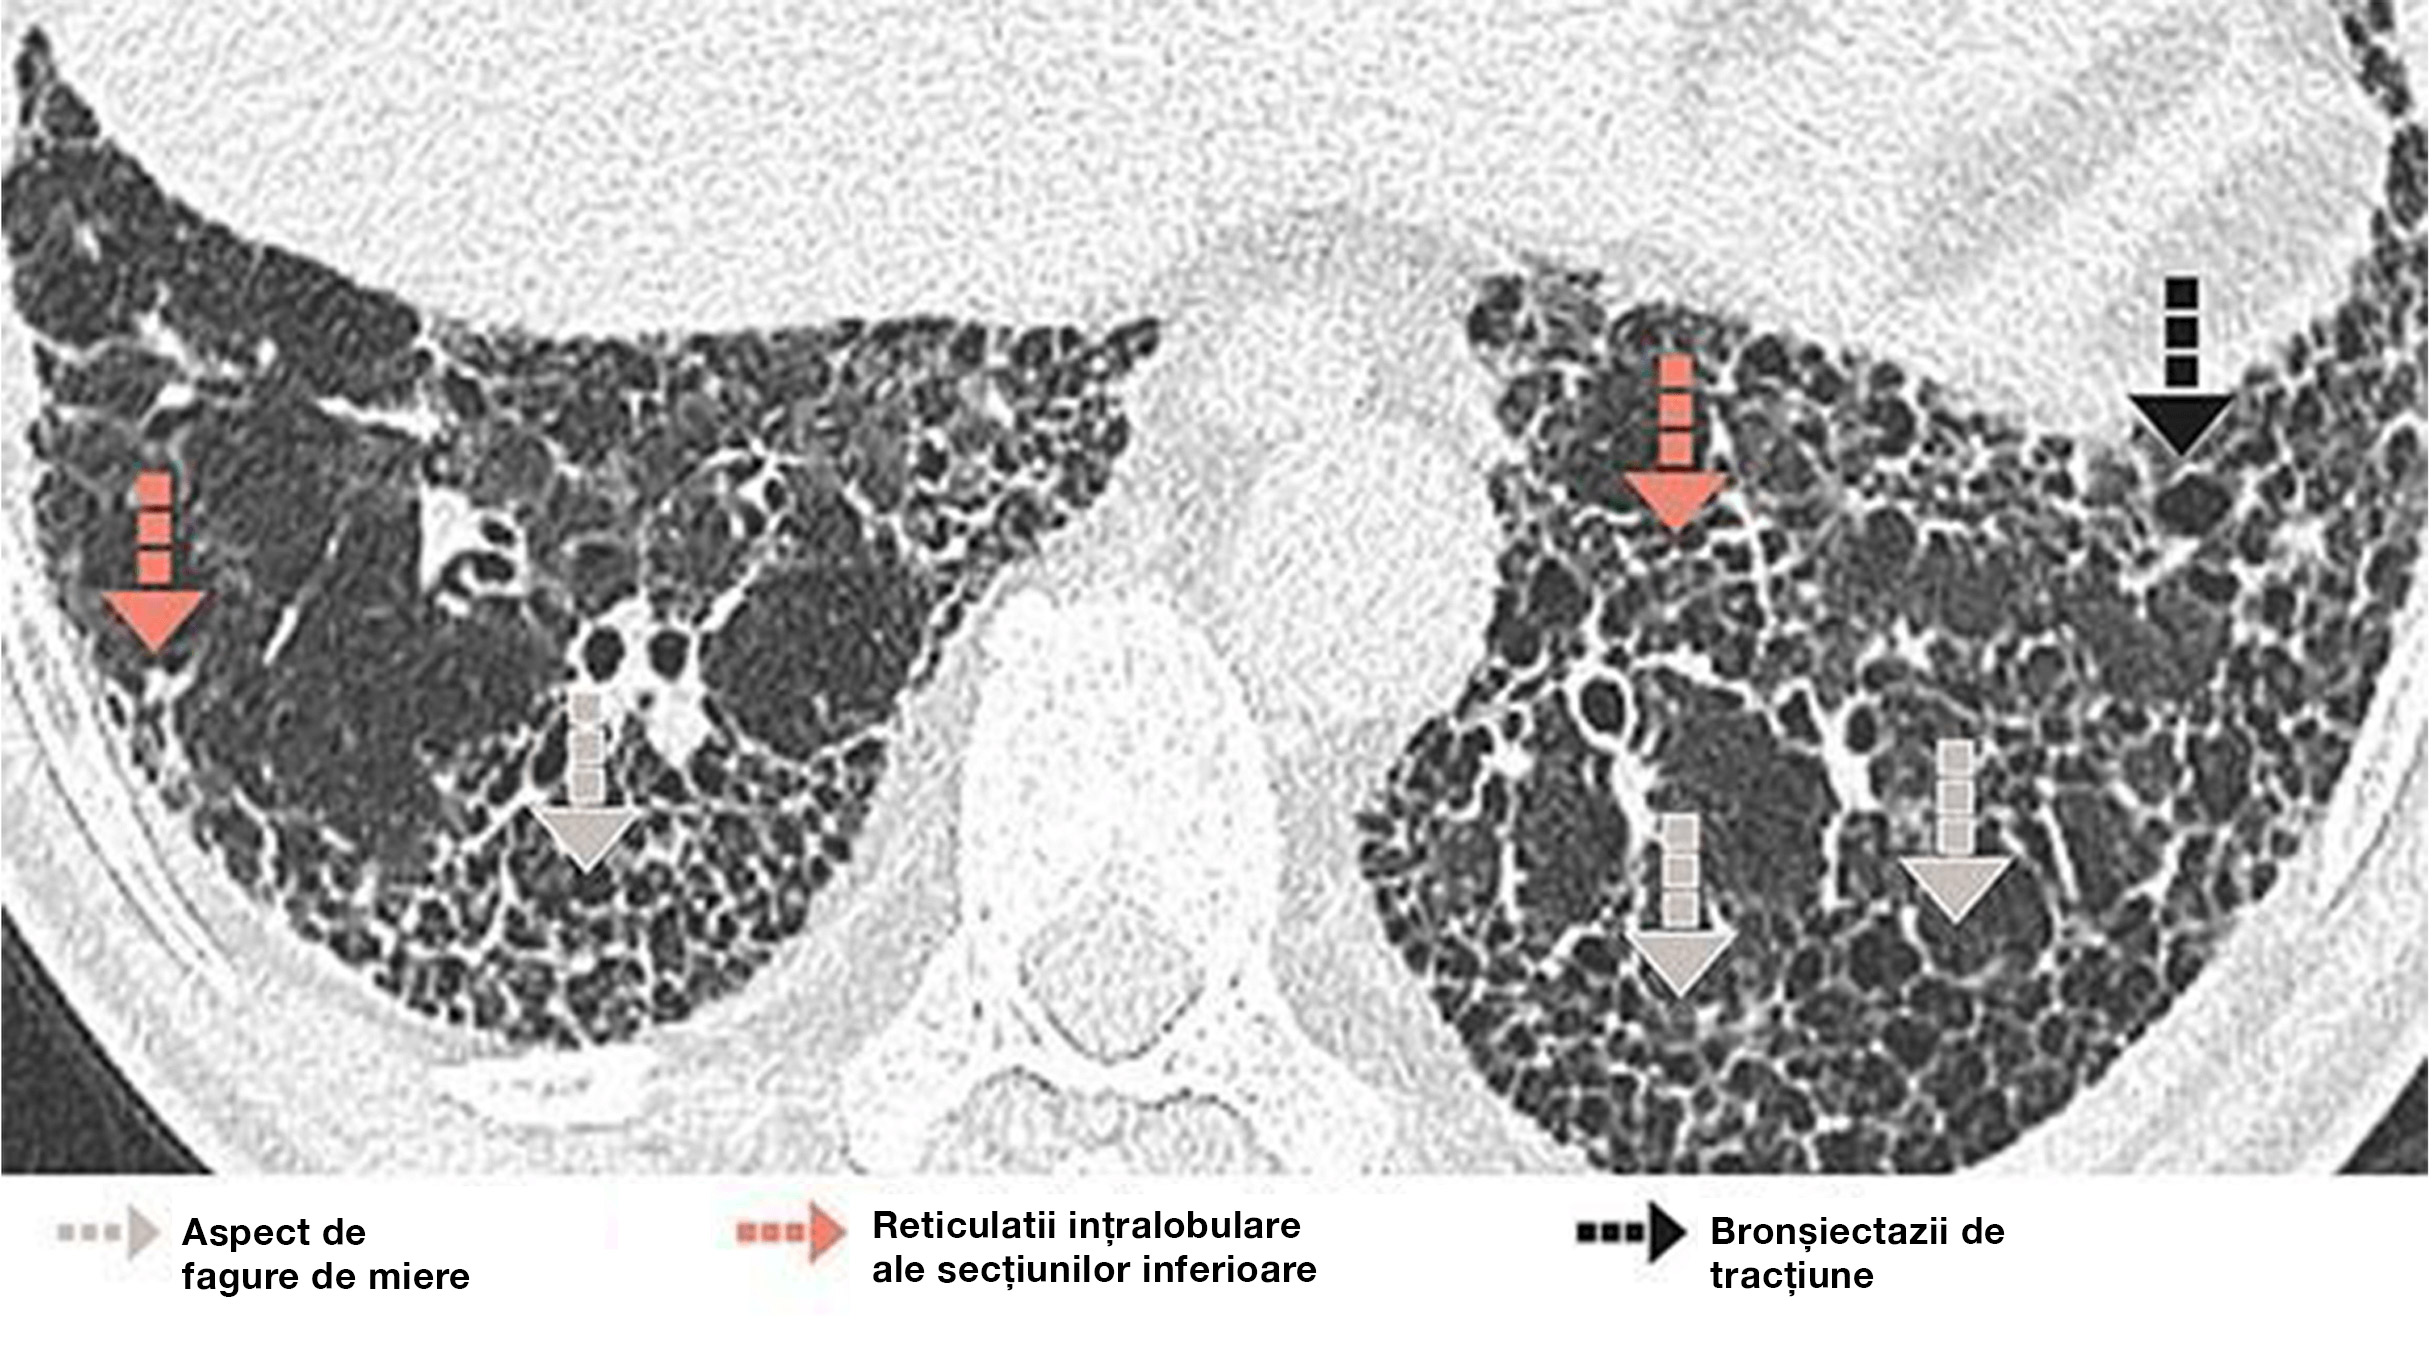

ASPECT DE FAGURE DE MIERE

Caracteristici

• Spații aeriene chistice grupate, cu pereți bine delimitați, măsurând 2–10 mm în diametru, ajungând uneori la 25 mm, de obicei în regiunile subpleurale

Semne asociate cu aspectul de fagure de miere

• Reticulații intralobulare

• Bronșiectazii de tracțiune și bronșiectazii

• Pierderea în volum a lobului pulmonar

• Distorsiunea scizurii pulmonare

Aspect de fagure de miere subpleural care formează mai multe straturi de chisturi la un bărbat de 73 de ani cu UIP